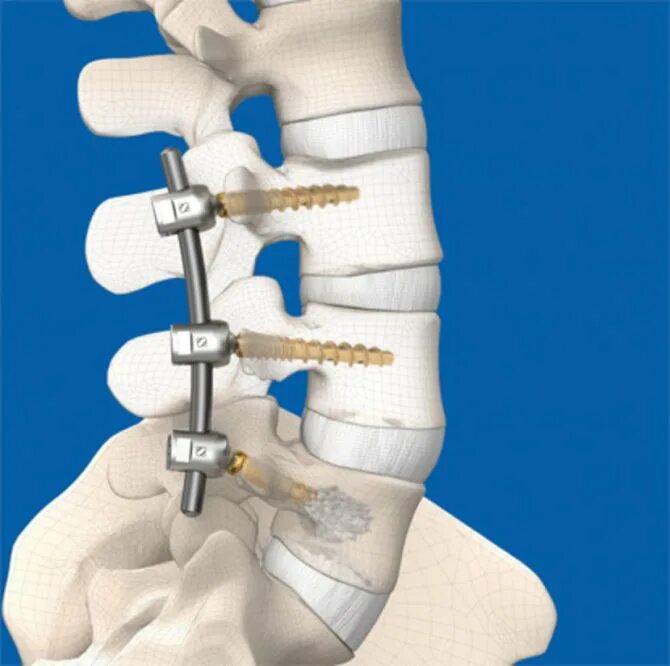

Операция на пояснично крестцовом отделе позвоночника